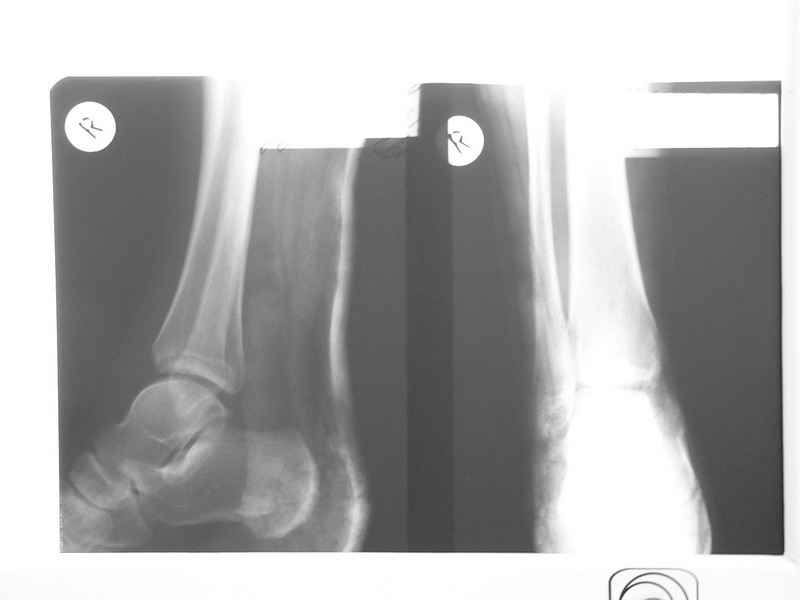

Совершенно верно был такой Пациент парень 29 лет. Только не 2 года а 4 года назад. Лечение растянулось на 2 этапа. На момент сообщения наложил окончатую гипсовую повязку, мазевые повязки, грануляции, закрыл свободной кожной пластикой. Через 2 месяца рана закрылась рубцом, гипс снял отправил на ЛФК. В течение года появлялся дважды - все ОК, нестабильности в суставе не было. Пациент работник УВД - его даже не комисовали. Обратился через 2 года после повторной травмы (опять мотоцикл) - открылся свищ в области медиальной лодыжки. Проведена операция - санация, рубец иссечен, пластика суральным лоскутом - состоятельная. Аппарат Илизарова на 2 месяца. Аппарат демонтировали опять ЛФК - Нестабильности в суставе нет, до сих пор трудится в органах... Опять подумывает о покупке мотоцикла.

К сожалению снимки нашел только после пластики. Р-гр где-то утерял посмотрю не работе.

Нашел в архиве форума снимки от 2007 года. Классная штука интернет! Александру Николаевичу отдельное спасибо!